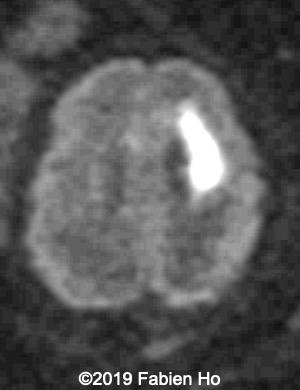

Axial DWI (diffusion weighted imaging): DWI is sensitive to cytotoxic cell edema, found in brain ischemia, among other things.

10

11

Our diagnosis was hence fetal stroke: probably ischemic stroke with secondary hemorrhagic transformation (hemorrhagic stroke could also be a possibility although the absence of mass effect and central lucency without hemorrhagic signal make this hypothesis less likely). Besides, in most pediatric and fetal clastic lesions, hemorrhage and ischemia are associated.